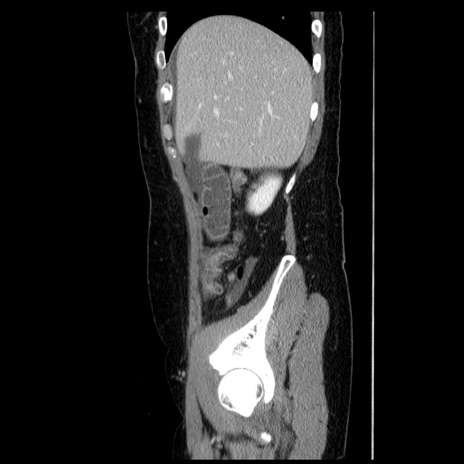

症例6(矢状断像)

【症例】50歳代女性

【主訴】下腹部痛

【既往歴】卵巣癌術後(8年前に当院で卵巣摘出)

【身体所見】 意識清明、腹部:平坦、腸蠕動音→、やや硬、下腹部自発痛・圧痛あり、反跳痛あり、筋性防御なし。

【データ】WBC 16000、CRP 0.01